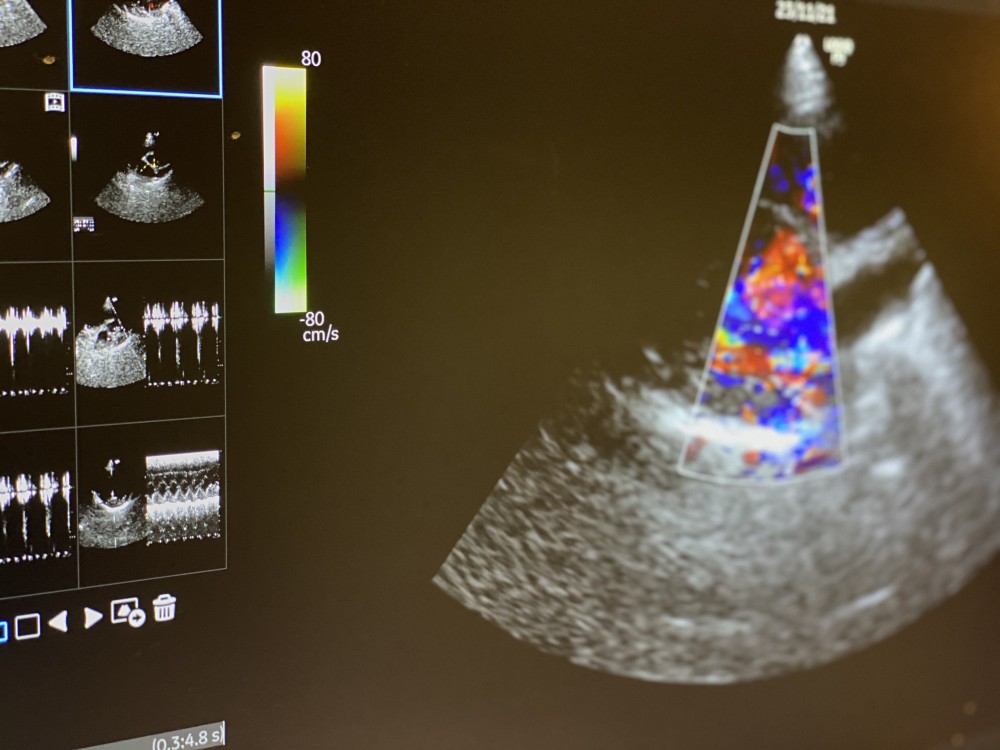

心臓病外来

獣医循環器学会 認定医(2018年試験合格)

獣医循環器学会 上席認定医(設立)

日本獣医循環器学会 理事